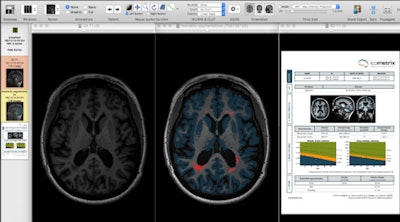

Segmentation techniques make it possible to extract very detailed, quantitative information from 3D datasets of the brain in MS patients. Left: Axial slice of MP-RAGE T1-weighted 3D set through the brain of MS patient. Middle: Image displays same slice after application of segmentation technique, showing MS lesions (or plaques) in red and cortical gray matter in blue. Right: Automatically generated report reveals exact volume of white matter lesions and cortical gray matter, and comparing the values of the patient against age- and sex-matched normal individuals. Such quantitative methods provide accurate follow-up and treatment monitoring of patients with multiple sclerosis because they allow sequential assessment of both white matter lesions and cortical gray matter atrophy. Figure courtesy of Dr. Paul Parizel, PhD.Longitudinal neuroimaging biomarkers take into account two (or more) MRI scans of the same subject, obtained at different time points, to calculate volume changes in brain volume. This enables assessment of MS patients for progressive brain shrinkage (atrophy), a parameter reflecting neuro-axonal and myelin loss, and it is increasingly being used as an outcome measure in MS treatment trials.